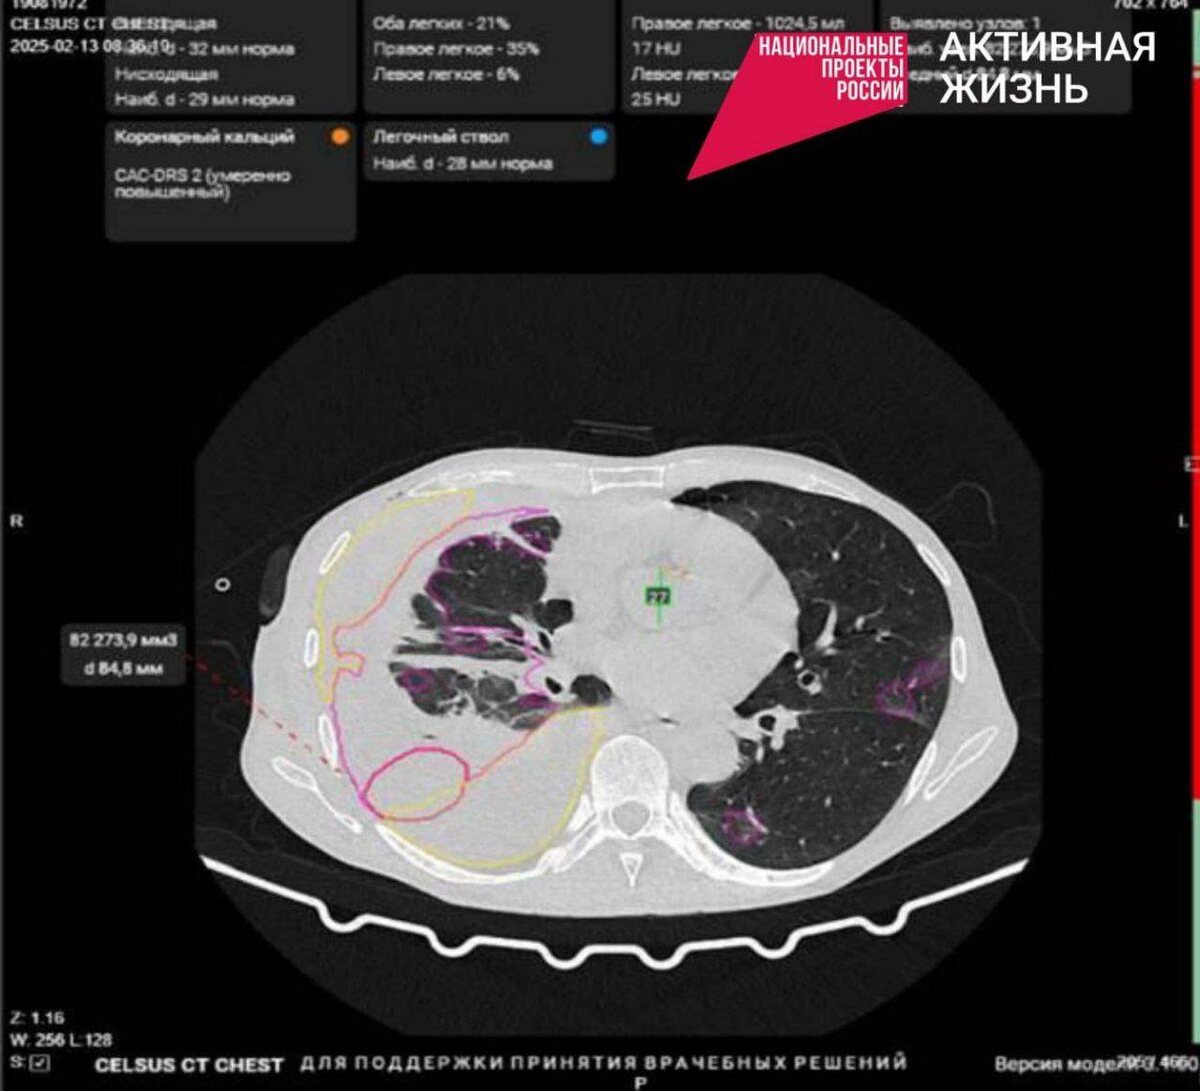

Врачи Борисовской ЦРБ впервые в регионе начали использовать искусственный интеллект при оказании медицинской помощи!

Нейросети находят признаки патологий на рентгенограммах, маммограммах, КТ, автоматически делают измерения, необходимые рентгенологу для подготовки заключения. Кроме того, ИИ может распознавать злокачественные новообразования на ранних стадиях, что увеличивает шансы на успешное лечение.

💬 «Искусственный интеллект не может заменить врача, а лишь помогает доктору выполнять его работу более качественно», — отмечает Алексей Дюмин, главный врач Борисовской районной больницы.